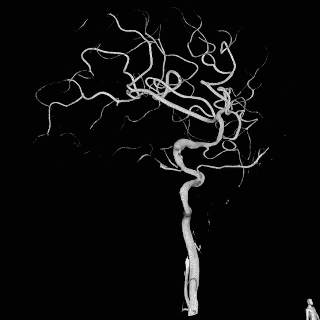

术前影像入院前头颅CTA提示:左侧颈内动脉C7段末端动脉瘤。